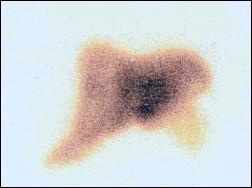

Gammagrafía hepática: Gran área hipocaptadora que ocupa la totalidad de sus 2/3 externos a excepción de su borde inferior, en relación a probable masa intrahepática. En el pool vascular se observa ausencia de perfusión en la masa tumoral (Fig. 4 y 5).

Fig 4.- Gammagrafía hepática: Gran área hipocaptadora

que ocupa los 2/3 externos del hígado a excepción

del borde inferior.

El aporte de los estudios por imágenes es medianamente significativo, así la ultrasonografía puede mostrar lesiones hepáticas hipodensas/hipoecoicas que corresponden a los trayectos seguidos por las larvas, también puede revelar el parásito en la vesícula o vias biliares (4,7). La TAC puede mostrar en el parénquima hepático dos tipos de lesiones: Areas hipodensas nodulares de 1-10 mm únicas o más frecuentemente múltiples, o areas hipodensas como túneles de disposición radiada resaltadas con el contraste altamente sugestivas de fasciolasis, igualmente puede evidenciar la fasciola en las vias biliares (4,10). Los hematomas subcapsulares se ven como una zona hipoecogénica o compleja por la presencia de coágulos sanguíneos. En la TAC el sangrado es isointenso en relación al parénquima hepático normal pero con el contraste el tejido hepático normal aumenta su densidad. La sangre fresca intrahepática no se oscurece, por lo tanto se observa en forma hipodensa (6) como se muestran en el presente caso. La resonancia magnética nuclear puede sugerir granulomatosis hepática y proporciona hallazgos similares a la TAC. La gammagrafía demuestra múltiples defectos intrahepáticos en aproximadamente 50% de los casos (7).